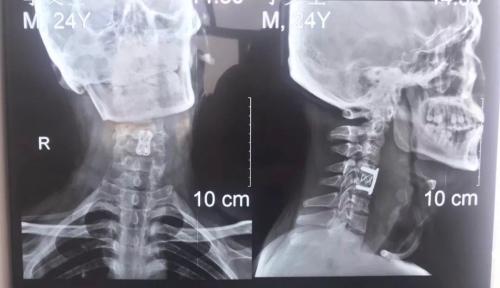

术前患者第四节颈椎骨折脱位

术后患者颈椎复位并通过钢板固定